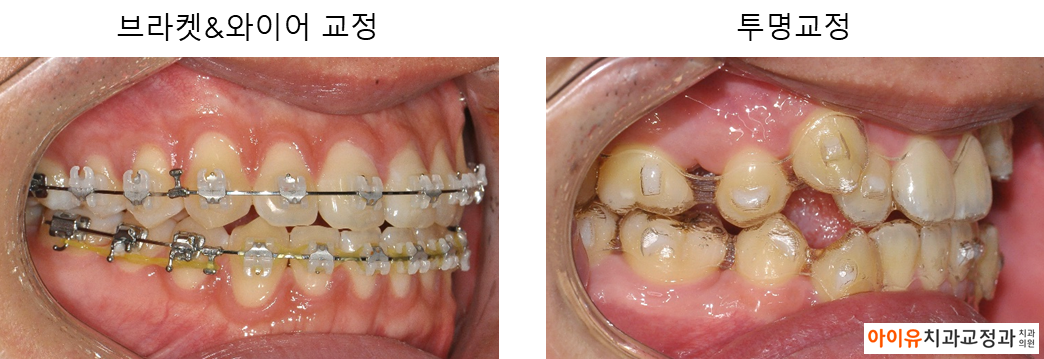

일명 철길이라고 불리는 브라켓과 달리 환자 스스로 끼웠다 뺐다 할 수 있는 투명한 재질의 장치를 투명교정 장치라고 일컫습니다.

아래는 지난 몇 년간 울산 아이유치과에서 진행한 인비절라인 치료결과, 전후사진 중 일부입니다.

위의 치료 결과에서 알 수 있듯 대부분의 경우에서 투명교정은 기존의 브라켓 교정과 동일한 효과를 얻을 수 있습니다.